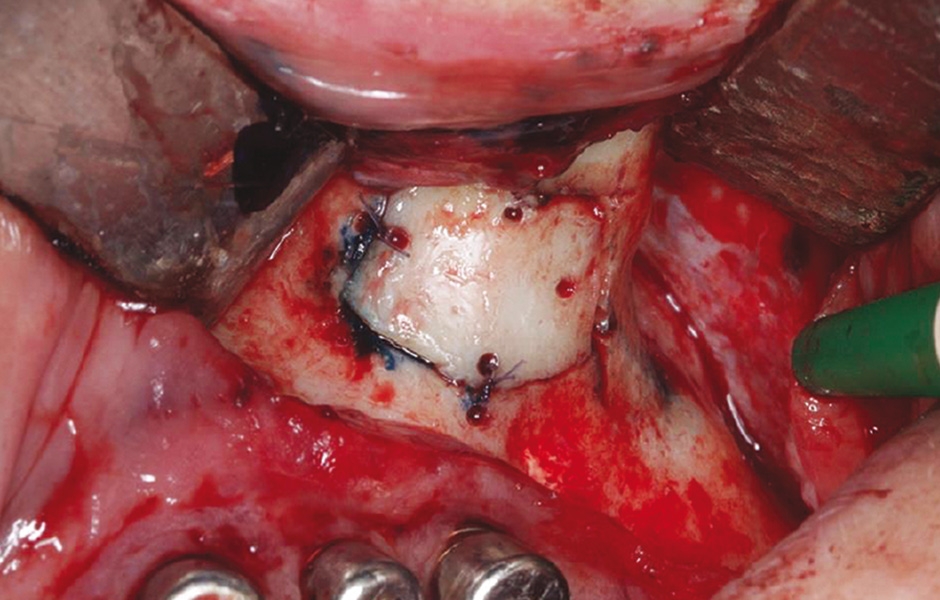

Obr. 2: Vytvoření kostního okénka mikropilkou včetně perforací pro fixaci resorbovatelnými stehy.

Obr. 3: Po vyjmutí kostěné lamely byla patrná zelenošedá masa; histologie potvrdila aspergilom.

Obr. 4: Po debridementu provedena fotodynamická dekontaminace laserem HELBO.

Obr. 5: Kostní víčko bylo znovu umístěno a původní implantáty odstraněny pro pokročilou periimplantitidu.